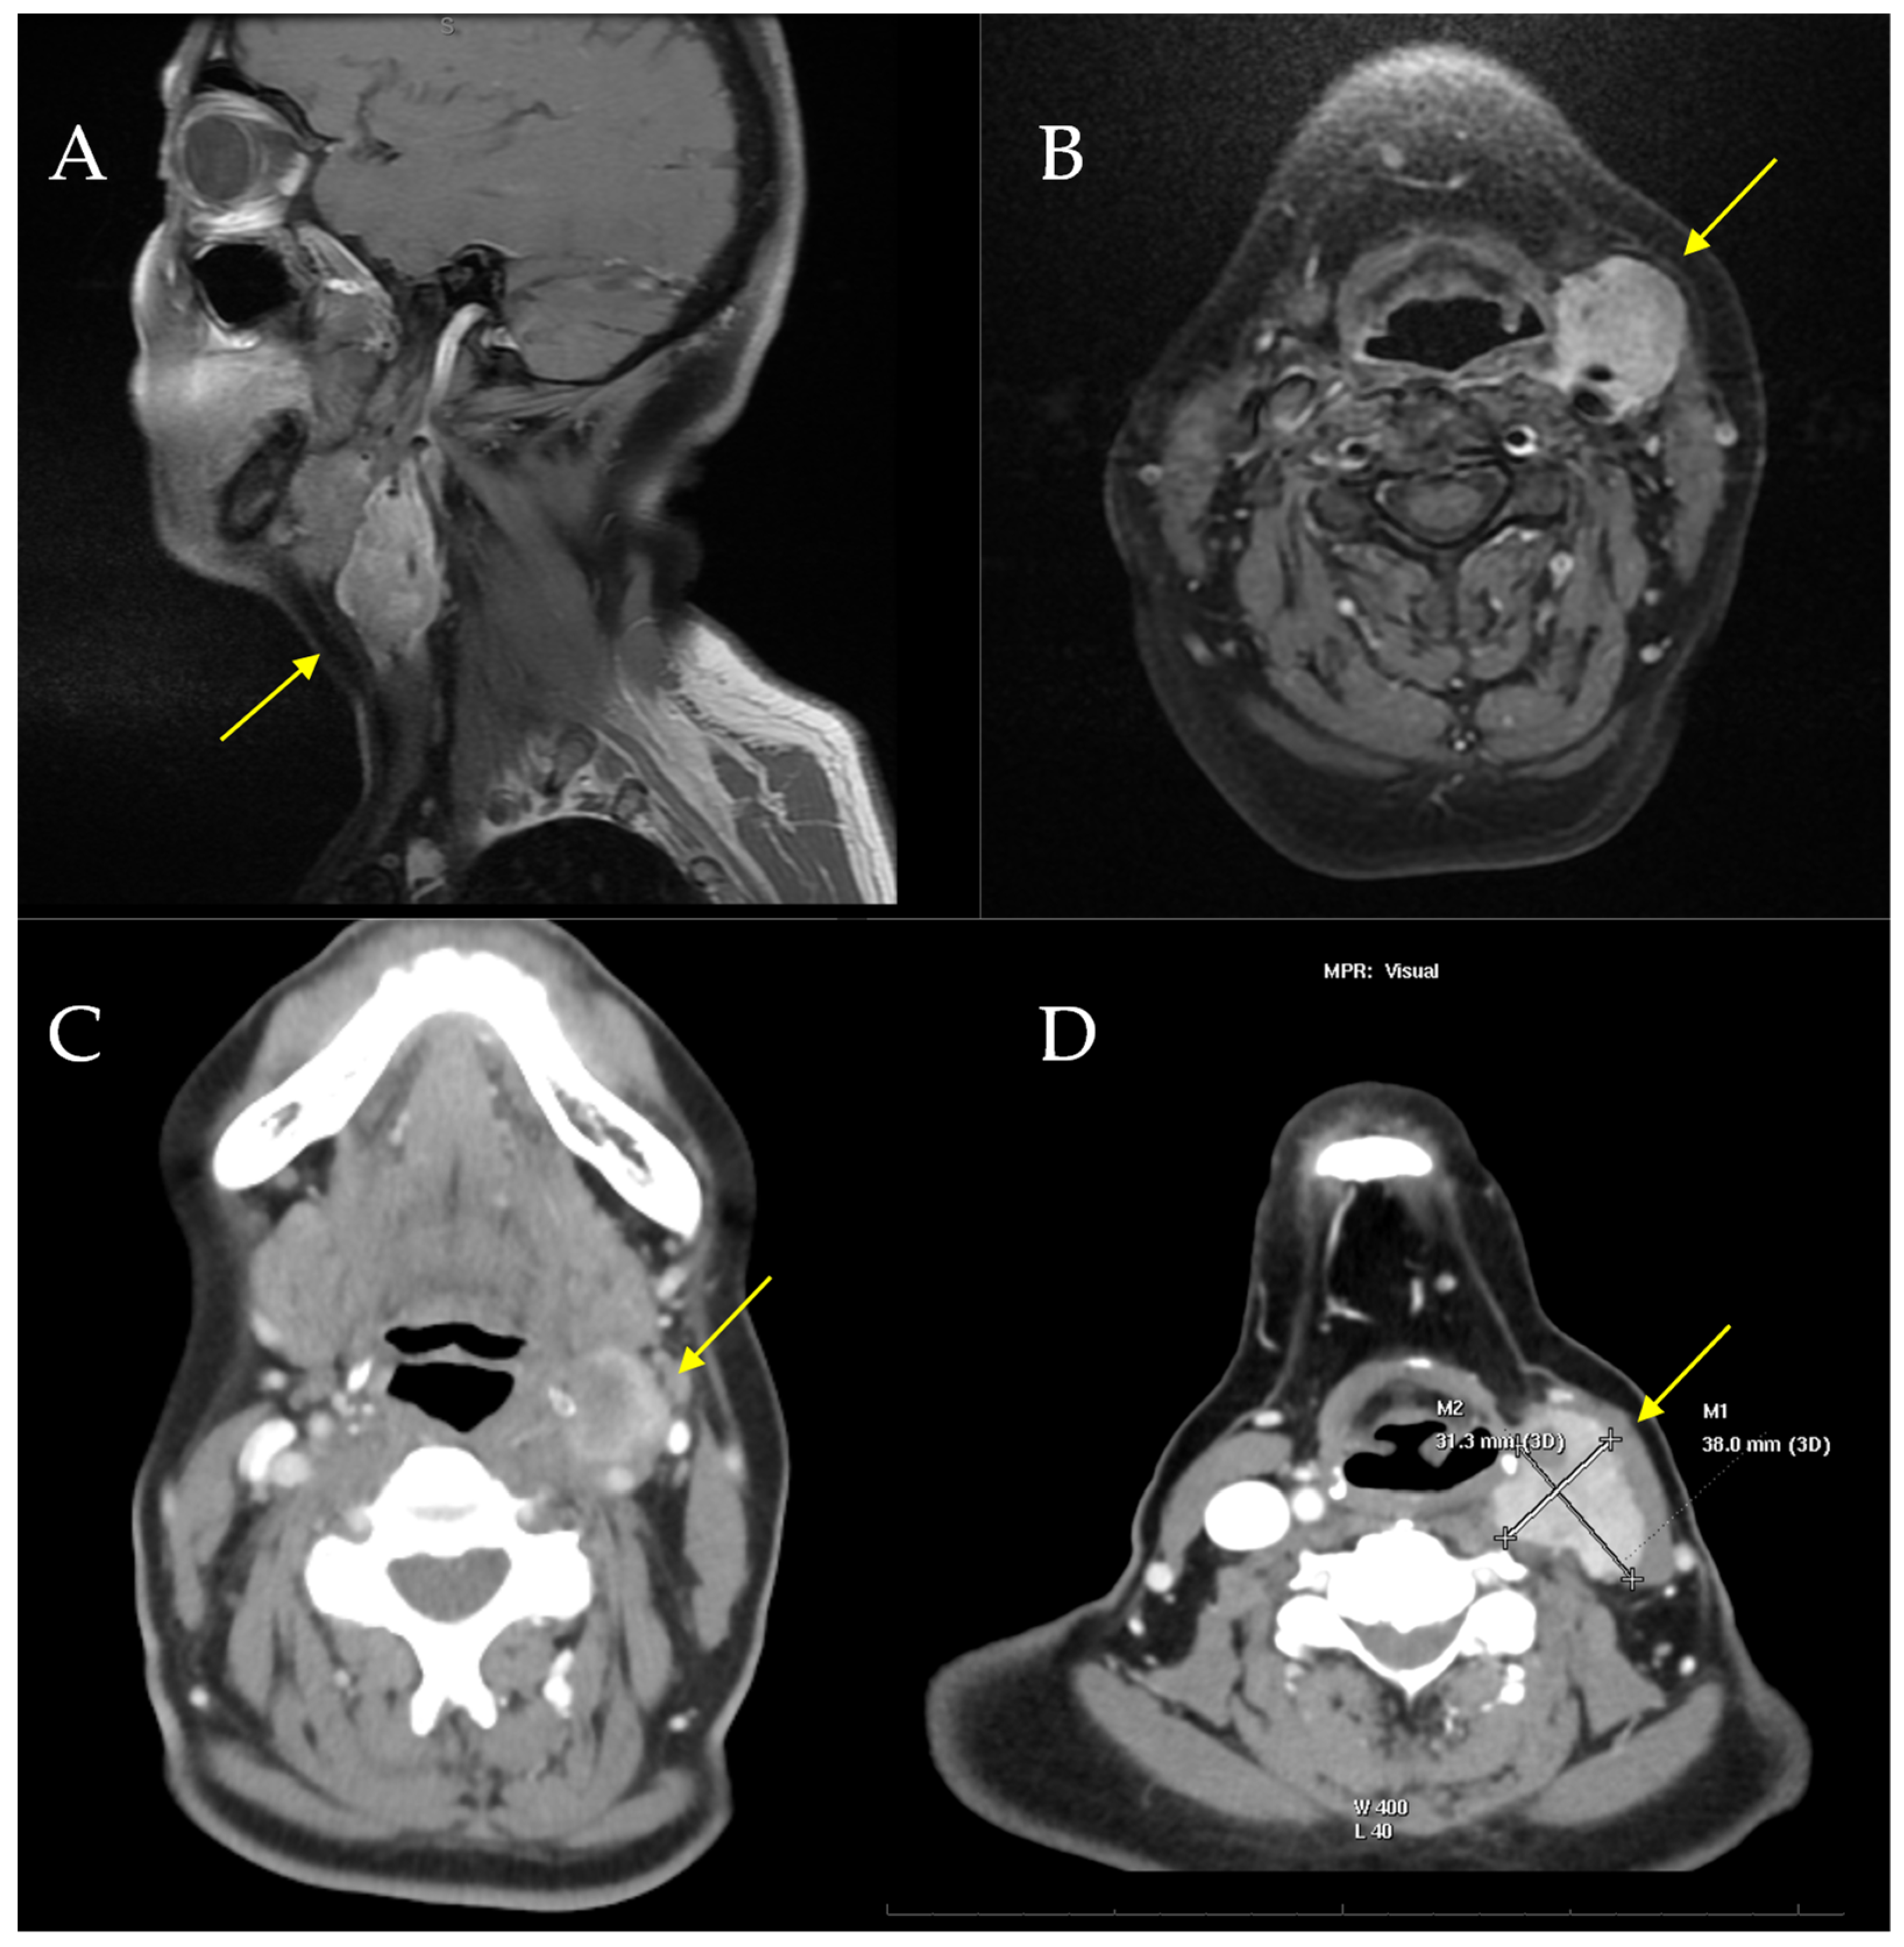

| 5 [our case] | 58/F | Left neck/4 cm | Positive: S100, SOX10, CD99 (weak/focal), Fli-1, and synaptophysin (focal). Negative: Melan-A, HMB-45, CKIT, AE1/AE3 | EWSR1 gene translocation | Surgery (radical resection) and radiotherapy | Yes: 48 mo | Yes: 36 mo | Died: 54 mo |